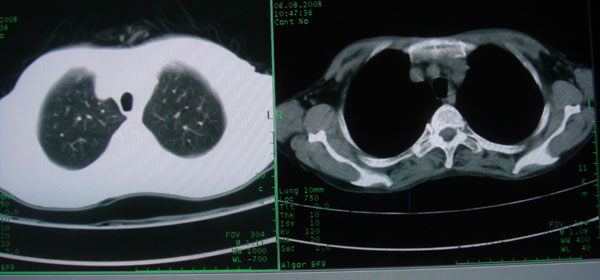

慢性支气管炎伴全小型肺气肿、支气管扩张、感染、间质纤维化。

慢性支气管炎伴支气管扩张、感染,间质纤维化。

慢性支气管炎伴全小叶型肺气肿、支气管扩张、感染、间质纤维化